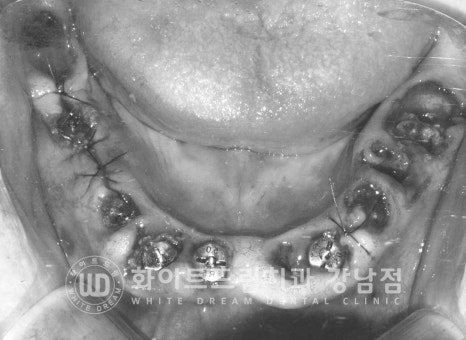

환자분의 수술 후 구내 사진입니다.

출혈이 조금 있어 흑백으로 처리를 했는데요.

대부분의 임플란트들은 잇몸뼈의 골 상태가 양호하여

2차 수술(임플란트를 겉으로 노출시키는 수술)까지 진행을 했고

앞서 안내드린 23번 임플란트 수술 부위만 1차 수술(잇몸뼈 안에 임플란트를 식립하는 수술)까지

진행을 하게 되었습니다.